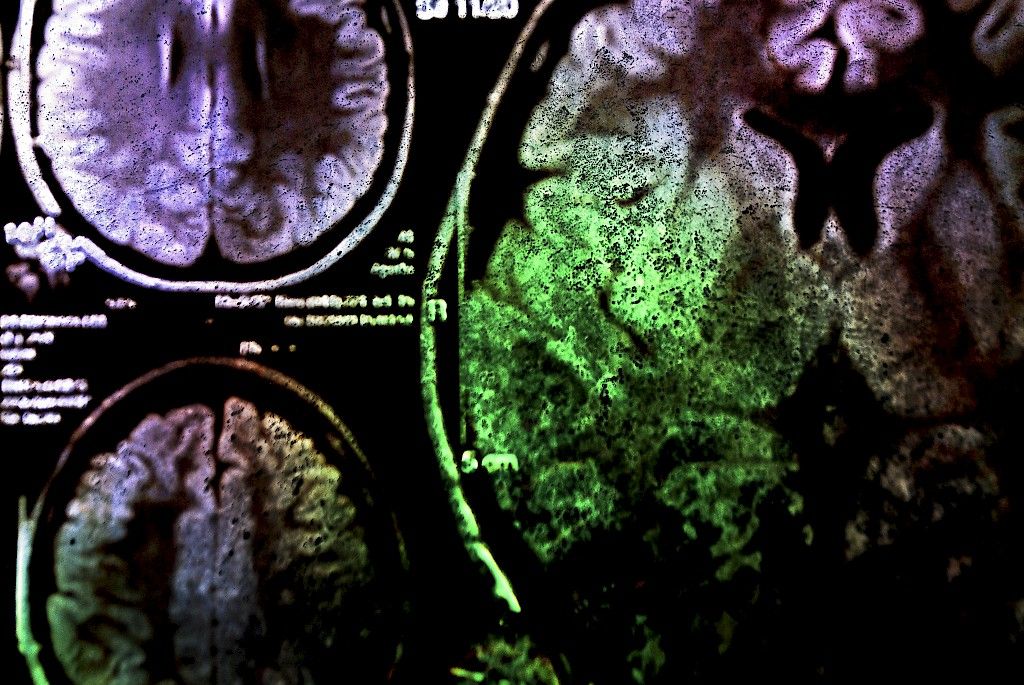

Tietokonetomografia ja magneettikuvaus mullistivat aivokasvainten diagnosoinnin 20–30 vuotta sitten. Niiden ansiosta kasvain diagnosoidaan usein jo aikaisessa vaiheessa. Lopullinen diagnoosi saadaan ottamalla näytepala kasvaimesta. Näytepala kertoo kasvaintyypin, sen lähtökudoksen, kasvunopeuden ja pahanlaatuisuuden.

Hoitojen jälkeen potilaan tilaa seurataan magneettikuvauksin. Seuranta voi jatkua vuosia, sillä kasvain voi uusia pitkänkin ajan jälkeen.